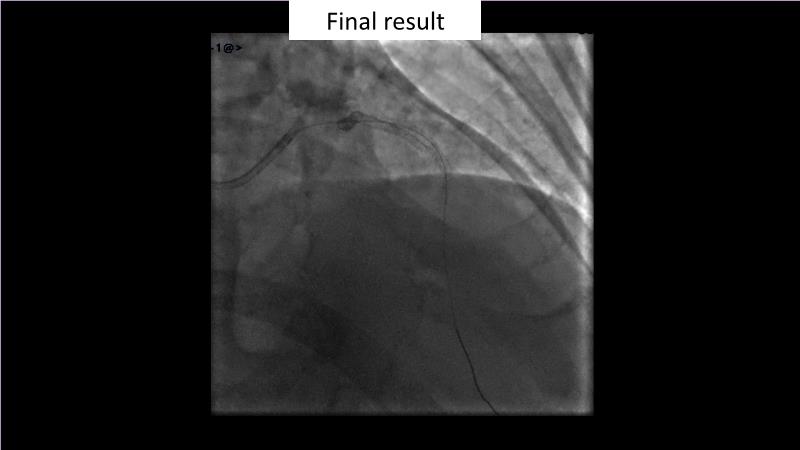

Browse this EuroPCR 2024 session to explore the safety and efficacy of sirolimus-coated balloons from pre-clinical data, review MagicTouch data from real-world populations with case-based examples, and learn about the MagicTouch sirolimus-coated balloon clinical programs. Discover insights and takeaways from the significance of the EASTBOURNE subgroups, and analyze the challenges and opportunities in PCI for diabetic patients.